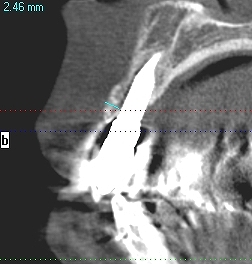

CTにより解剖学的形態を避け、安全に顎骨内にインプラントを埋入することが大切です。 かなり厳しいケースもあります。| |広島市安佐南区の歯科医院 CTにより解剖学的形態を避け、安全に顎骨内にインプラントを埋入することが大切です。 かなり厳しいケースもあります。 トップ お知らせ・ブログ CTにより解剖学的形態を避け、安全に顎骨内にインプラントを埋入することが大切です。 かなり厳しいケースもあります。 CTにより解剖学的形態を避け、安全に顎骨内にインプラントを埋入することが大切です。 かなり厳しいケースもあります。 Web診療予約 初めての方へ 選ばれ続ける理由 院内設備について 歯が痛いしみる一般歯科 歯がぐらぐらする歯周病 健康な歯を保ちたい予防歯科 子供の虫歯予防をしたい小児歯科 銀歯をセラミックに審美歯科 白い歯を目指しませんか?ホワイトニング 矯正専門医がいるので安心矯正歯科 抜けた歯を補いたいインプラント・入れ歯 医院案内 スタッフ紹介 メリィハウス歯科クリニックオフィシャルホームページ ラベンダー歯科クリニックオフィシャルホームページ お知らせ・ブログ ホーム 診療科目 一般歯科 歯周病治療 予防治療 小児歯科 審美治療 ホワイトニング 矯正歯科 入れ歯・インプラント マウスピース矯正 初めての方へ 院長・スタッフ 設備紹介 医院案内・アクセス メニューを閉じる